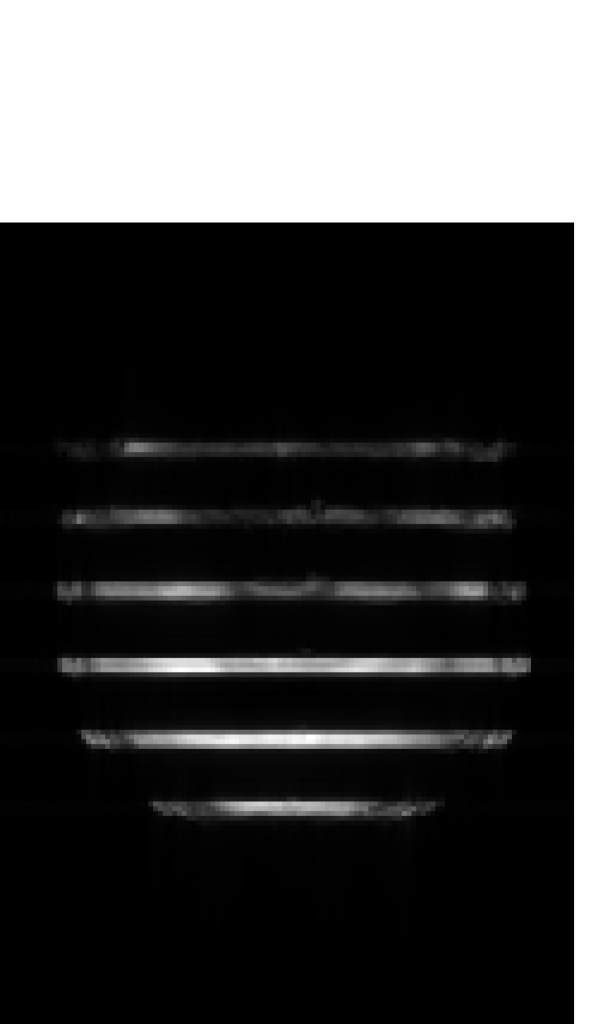

Figure 4 shows the results of the design of RF pulses for simultaneous excitation of two, four and six equidistant slices with a separation of and a thickness ; see Fig. 1(b). The computational effort in all cases is similar to that in the single-slice case. The corresponding computed pulses are shown in Figs. 4(a) to LABEL:sub@fig:sms:a6. A graphical analysis shows that instead of higher amplitudes, the optimization distributes the total RF power (which increases with the number of slices) more uniformly over the pulse length. A central section of the corresponding optimized slice profiles are given in Figs. 4(d) to LABEL:sub@fig:sms:b6. It can be seen that all slices have a sharp profile which does not deteriorate as the number of slices increases (although it decreases slightly farther from the center and the bandwidth is slightly reduced). These results are validated by the experimental phantom measurements using the computed pulses: Figs. 4(g) to LABEL:sub@fig:sms:c6 show the reconstructed excitation inside the phantom, while Figs. 4(j) to LABEL:sub@fig:sms:d6 show the measured slice profiles along a cut parallel to the -axis in the center of the previous images.

as well as the mean absolute error (MAE) with respect to the ideal (unfiltered) slice profiles for the in-slice and the out-of-slice regions. While both methods lead to a linear increase of the total energy with the number of slices, the peak amplitude increases more slowly for the OC pulses than for the conventional pulses. Furthermore, we remark that the peak B1 amplitude for four, five and six slices remain similar. Regarding the corresponding slice profiles, the OC pulses lead to a significantly lower MAE in both the in-slice and out-of-slice regions compared to the SLR pulses. Visual inspection of Figs. 4(d) to LABEL:sub@fig:sms:b6 shows that this is due to the fact that the out-of-slice ripples are concentrated around the in-slice regions while quickly decaying away from them.